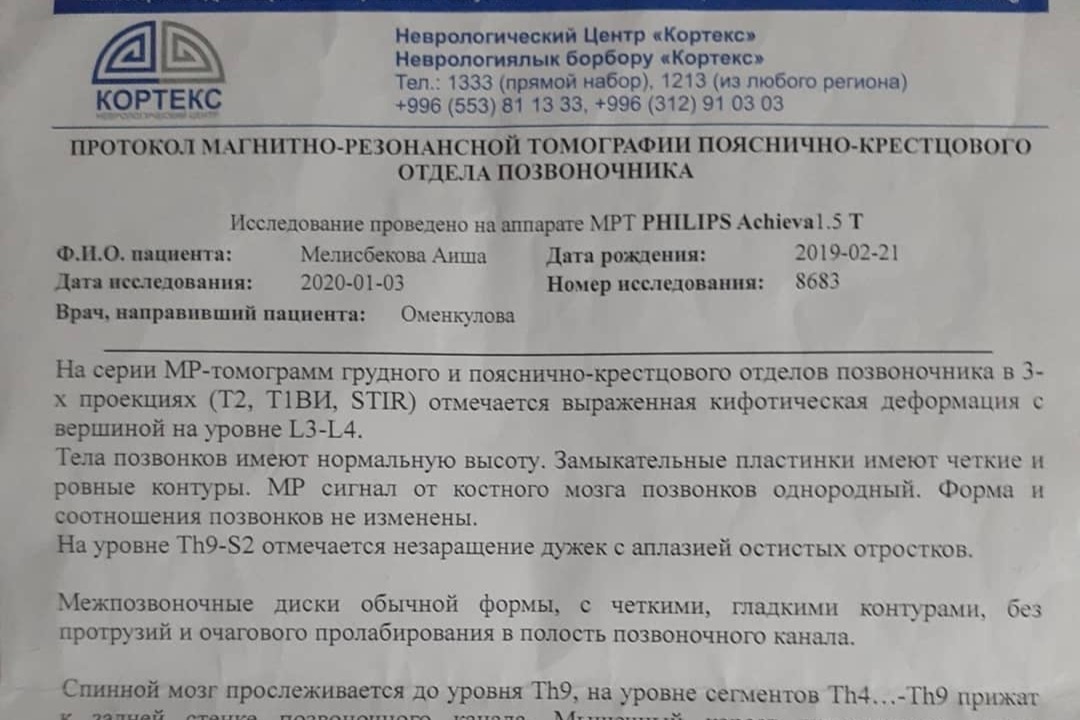

A️isha Melisbekoba was born with Spina Bifida myelomeningocele, syndrome of fixed spinal cord at 29 weeks. Doctors say that people born with this diagnosis will not live long. But with proper treatment on time she will survive. So far she had 2 operations on her spinal cord. Her spine is torn, spinal cord is protruding, and there is water in 1/3 of her head.

Diagnosis: CMD of the central nervous system Spina bifida myelomeningocele, fixed spinal cord syndrome. Kyphotic spinal deformity. Internal hydrocephalus, Arnold-Chiari type 2 anomaly. Peripheral paralysis of both legs. CHD, DMPP. CHF of the MPS hydronephrotic transformation of the left kidney, incomplete doubling of the left kidney. Urine and callus retention. Condition after: ventriculo-peritoneal shunting from 04/16/2019. And excision of the spinal hernia from 10/29/2019.

A️isha Melisbekoba was born with Spina Bifida myelomeningocele, syndrome of fixed spinal cord at 29 weeks. Doctors say that people born with this diagnosis will not live long. But with proper treatment on time she will survive. So far she had 2 operations on her spinal cord. Her spine is torn, spinal cord is protruding, and there is water in 1/3 of her head.

Diagnosis: CMD of the central nervous system Spina bifida myelomeningocele, fixed spinal cord syndrome. Kyphotic spinal deformity. Internal hydrocephalus, Arnold-Chiari type 2 anomaly. Peripheral paralysis of both legs. CHD, DMPP. CHF of the MPS hydronephrotic transformation of the left kidney, incomplete doubling of the left kidney. Urine and callus retention. Condition after: ventriculo-peritoneal shunting from 04/16/2019. And excision of the spinal hernia from 10/29/2019.